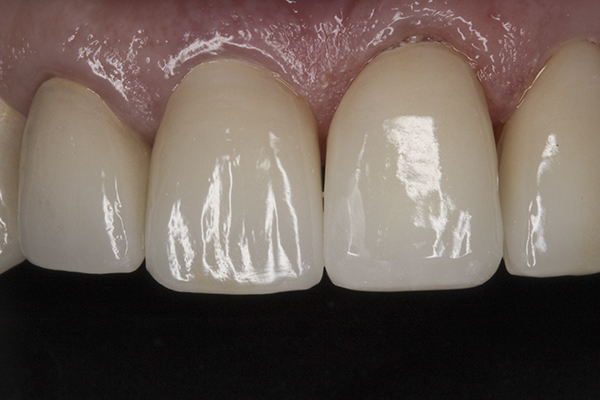

(39.) Postoperative anterior, close-up view.

Figure 39